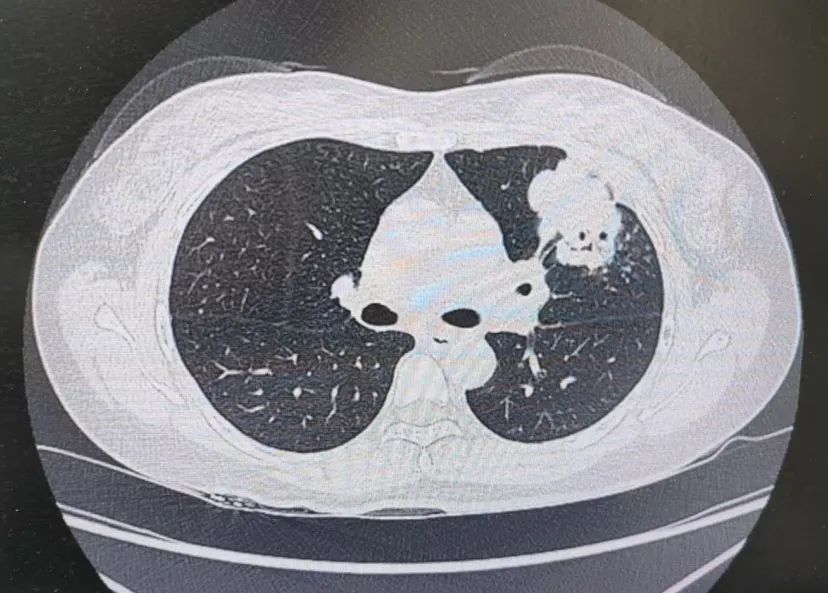

患者肺部CT影像

“一般來(lái)說(shuō),肺炎經(jīng)過(guò)一周的抗感染治療,病灶會(huì)有所吸收。但陳女士的肺部陰影紋絲不動(dòng),這種情況必須提高警惕。”宋剛主任團(tuán)隊(duì)立即啟動(dòng)了更深入的“三部精準(zhǔn)診斷”程序:

3、CT引導(dǎo)下穿刺活檢:病理診斷為左肺上葉腺癌。

肺炎型肺癌,因其影像學(xué)表現(xiàn)與普通肺炎極為相似,臨床上誤診率極高。然而確診僅是第一步。宋剛主任當(dāng)天即召集腫瘤科、病理科、影像科等多學(xué)科專家會(huì)診,為陳女士制定個(gè)體化治療方案。